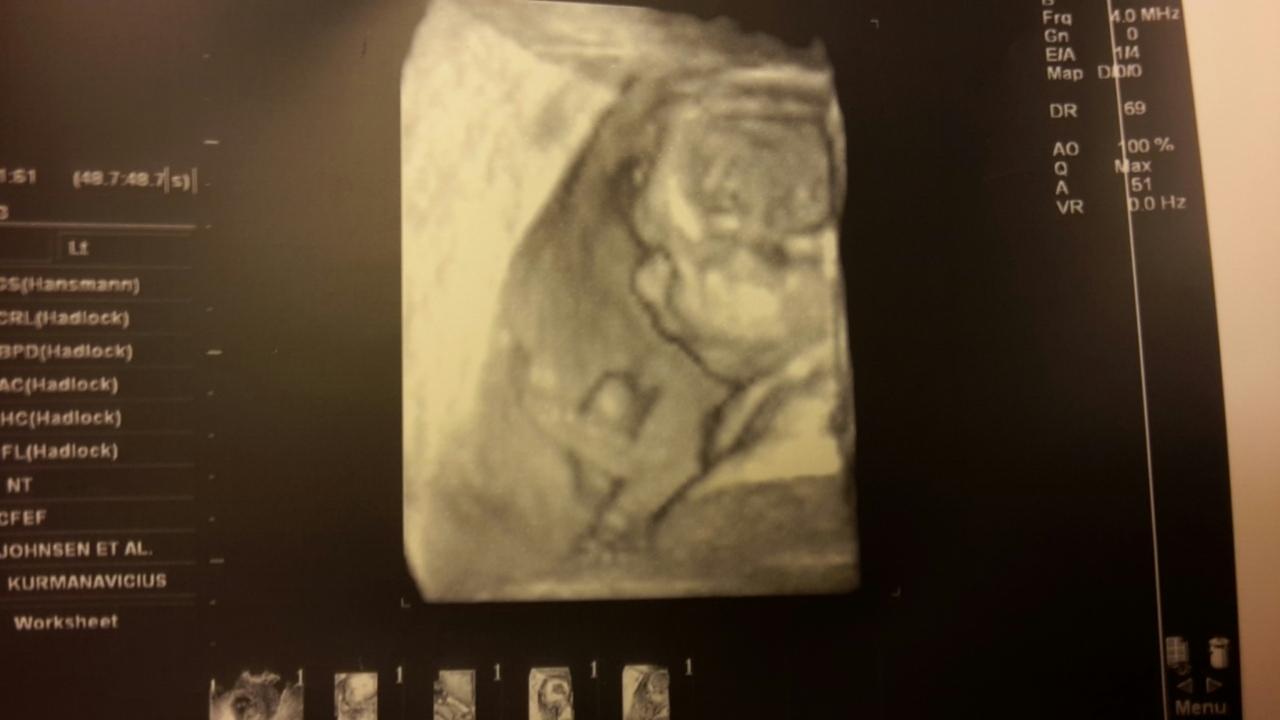

Krásné fotečky a jak ti je? 🙂